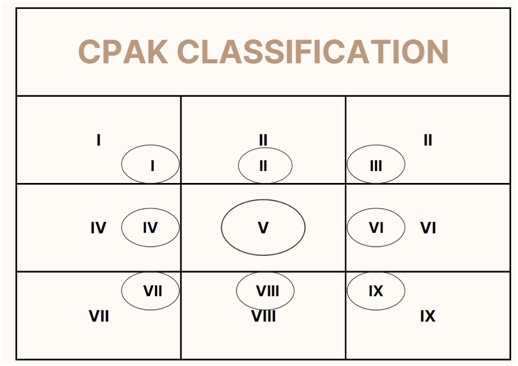

Recently, knee alignment has been found to fall into one of 9 categories and each patient who undergoes a knee replacement would fall in one of these 9 categories. The aim of conventional TKA was to get a perfect 180-degree alignment on standing view which would correspond to CPAK category V. In spite of good alignment, a section of patients arestill unhappy, and the hypothesis was that the change of CPAK category leads to dissatisfaction.

The principle of robotic TKA is to move patients towards better alignment but retaining the patient in the same CPAK category so that there is improvement in the patient’s functional outcome and satisfaction rates. This approach is to ensure that “One size fits all” approach is not undertaken and truly individualizing the care to each patient’s needs. This technique and philosophy were advocated by Dr. Johan Bellemens group in 2021 and now evidence is emerging that the CPAK philosophy helps patient achieve better satisfaction rates and our experience of more than 100 robotic knees are pointing towards the same outcome.